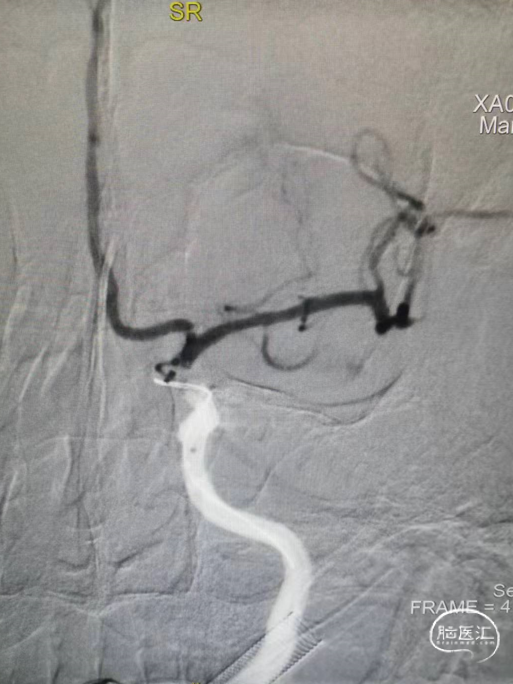

➢术后即刻影像

术后颈内动脉末端血流通常,左侧大脑前动脉和大脑中动脉显影正常。